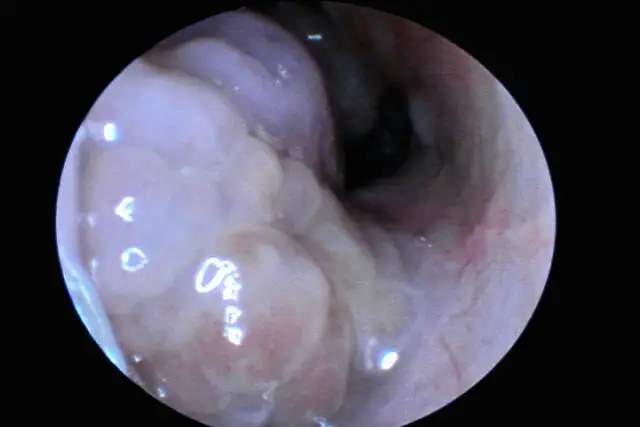

鼻息肉是临床常见的耳鼻喉科疾病,是鼻腔及鼻窦黏膜水肿、增生形成的炎性肿物,多生长在鼻腔外侧壁、鼻窦开口附近。典型症状包括持续性鼻塞、流涕、鼻部胀痛,严重时可造成鼻腔完全堵塞、嗅觉减退甚至丧失。很多患者治疗后仍反复出现,十分困扰,鼻息肉易复发主要有以下几方面原因: